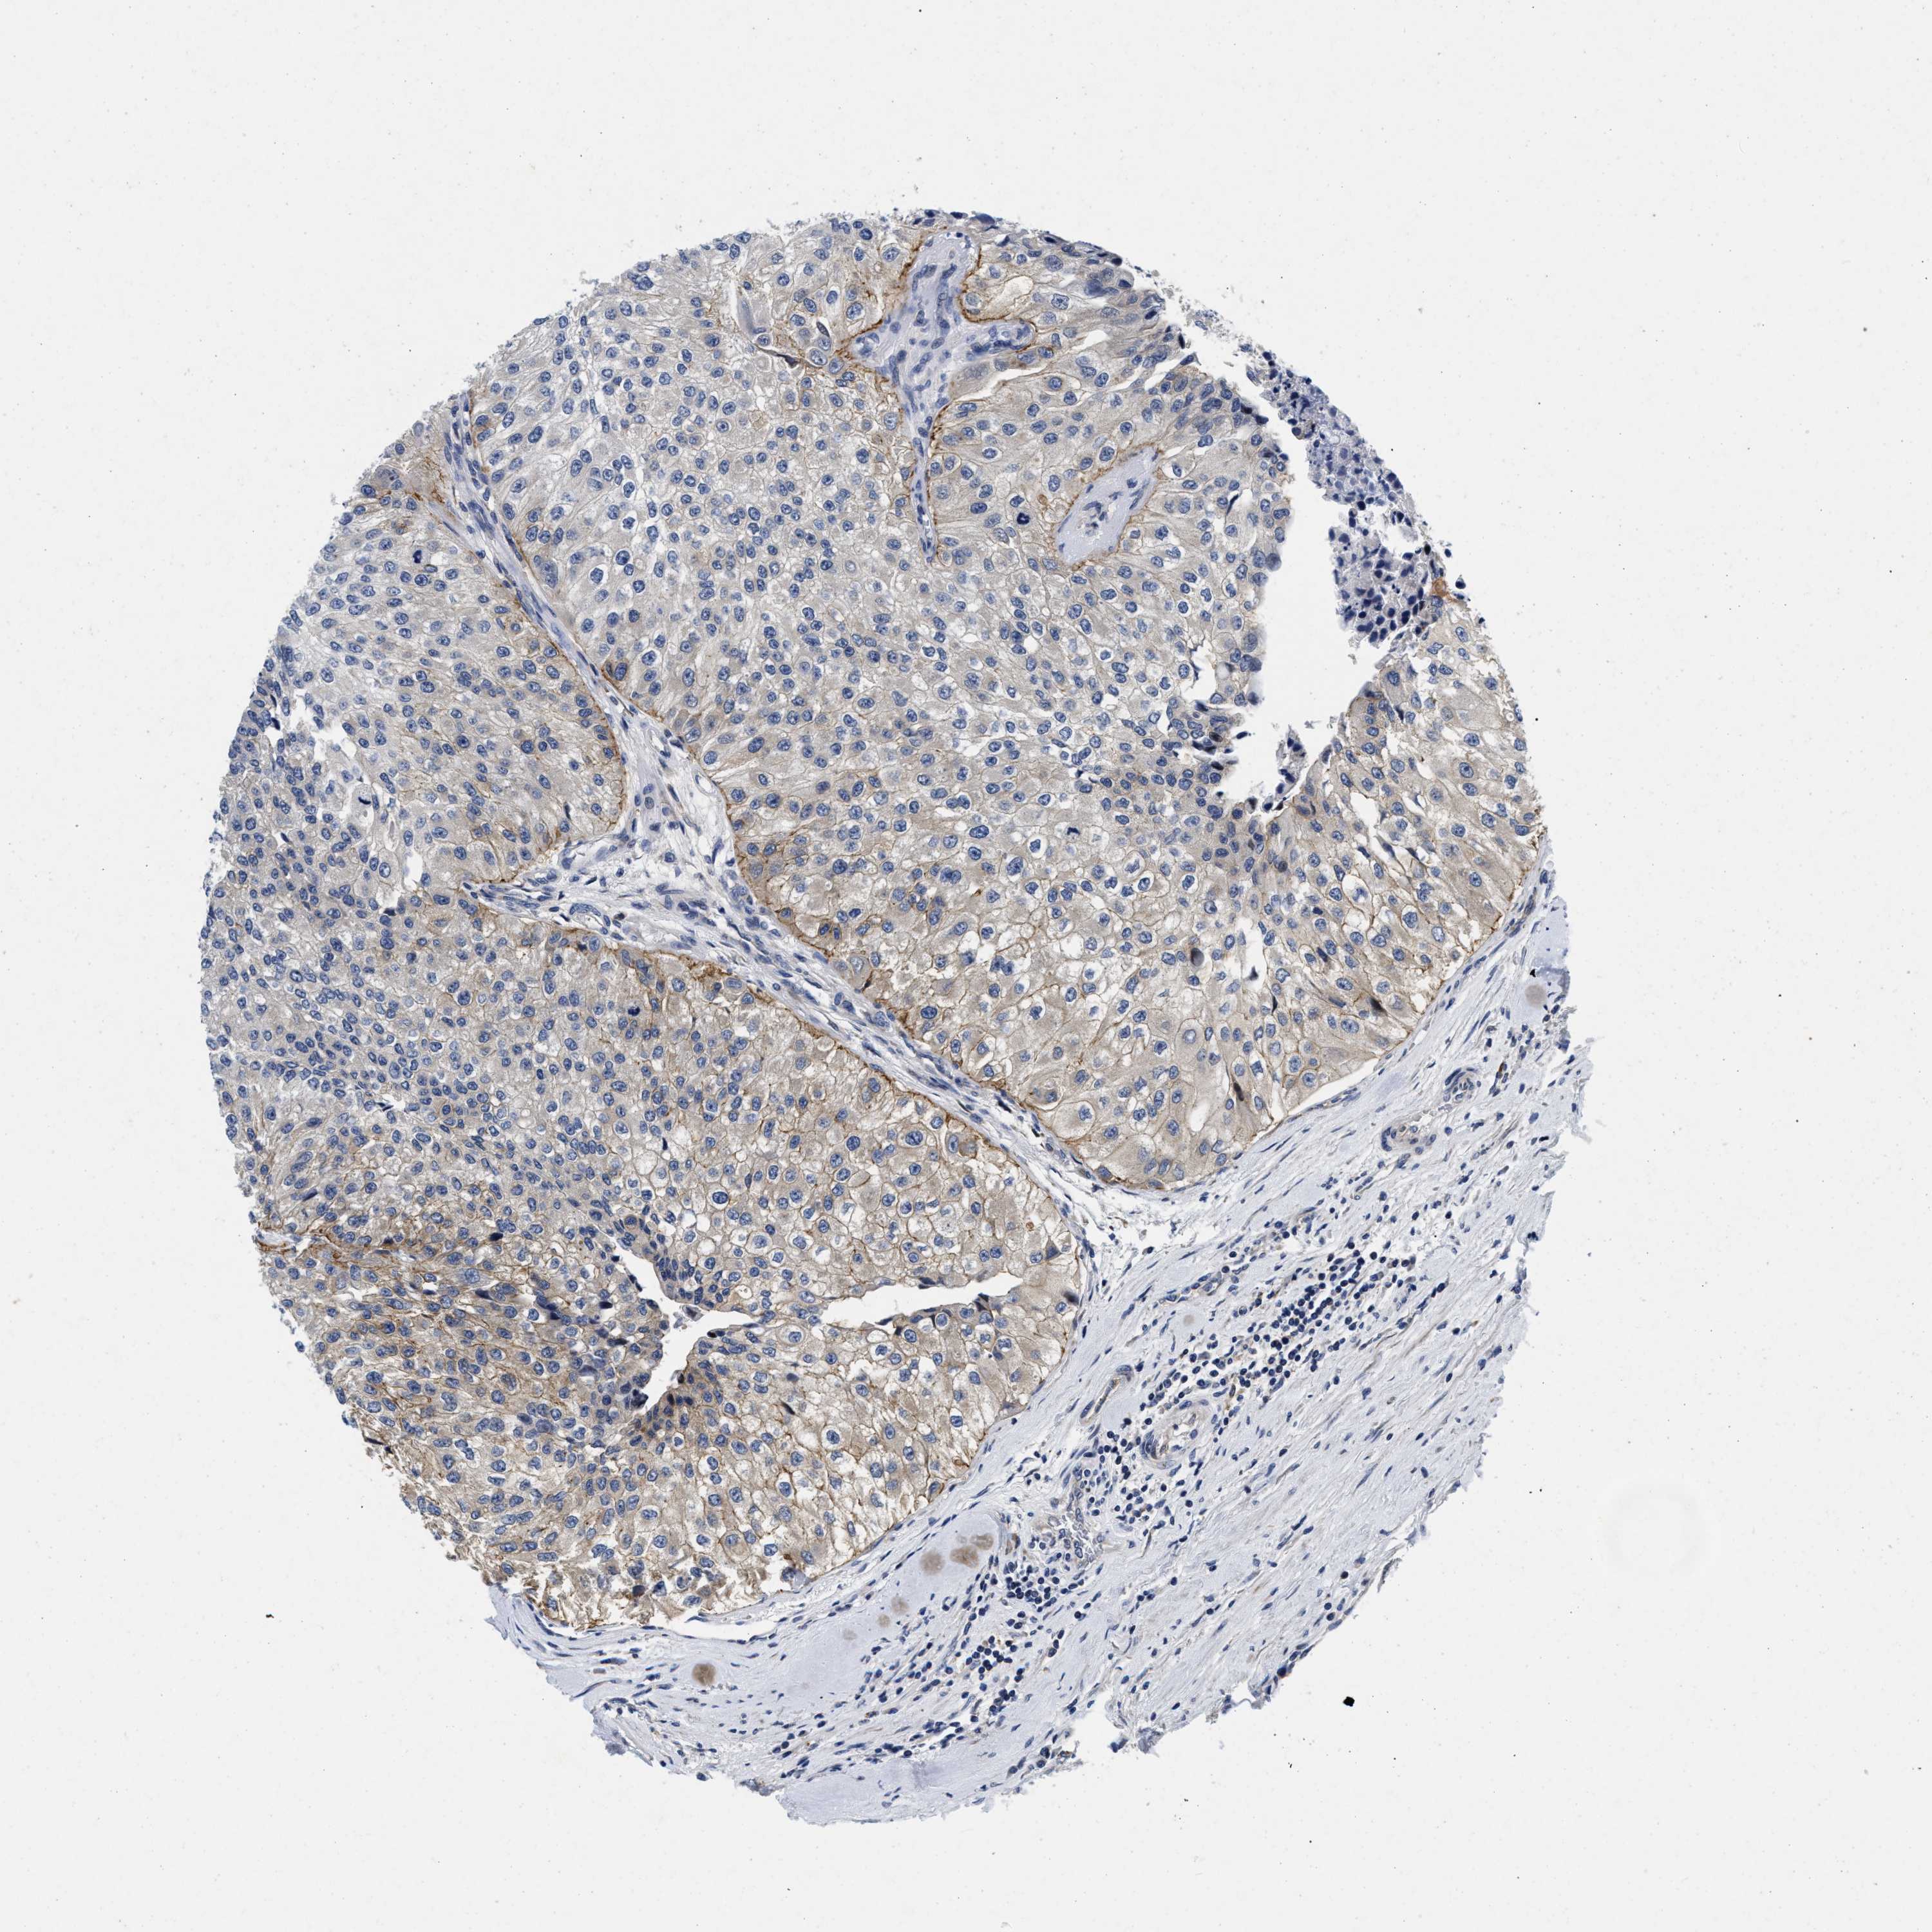

UROTHELIAL CANCER - Protein expressioni

A mouse-over function shows sample information and annotation data. Click on an image to view it in a full screen mode. Samples can be filtered based on level of antibody staining by selecting one or several of the following categories: high, medium, low and not detected. The assay and annotation is described here.

Antibody stainingi

Antibody staining in the annotated cell types in the current human tissue is reported as not detected, low, medium, or high, based on conventional immunohistochemistry profiling in selected tissues. This score is based on the combination of the staining intensity and fraction of stained cells.

Each image is clickable and will lead to virtual microscopy that enables deeper exploration of all samples and also displays staining intensity scores, fraction scores and subcellular localization as well as patient and tissue information for each sample.

Antibody HPA007256

Antibody HPA028732

Staining

High

Medium

Low

Not detected

Intensity

Strong

Moderate

Weak

Negative

Quantity

>75%

75%-25%

<25%

None

Location

Nuclear

Cytoplasmic/membranous

Cytoplasmic/membranous,nuclear

Urothelial carcinoma, Low grade

Urothelial carcinoma, High grade